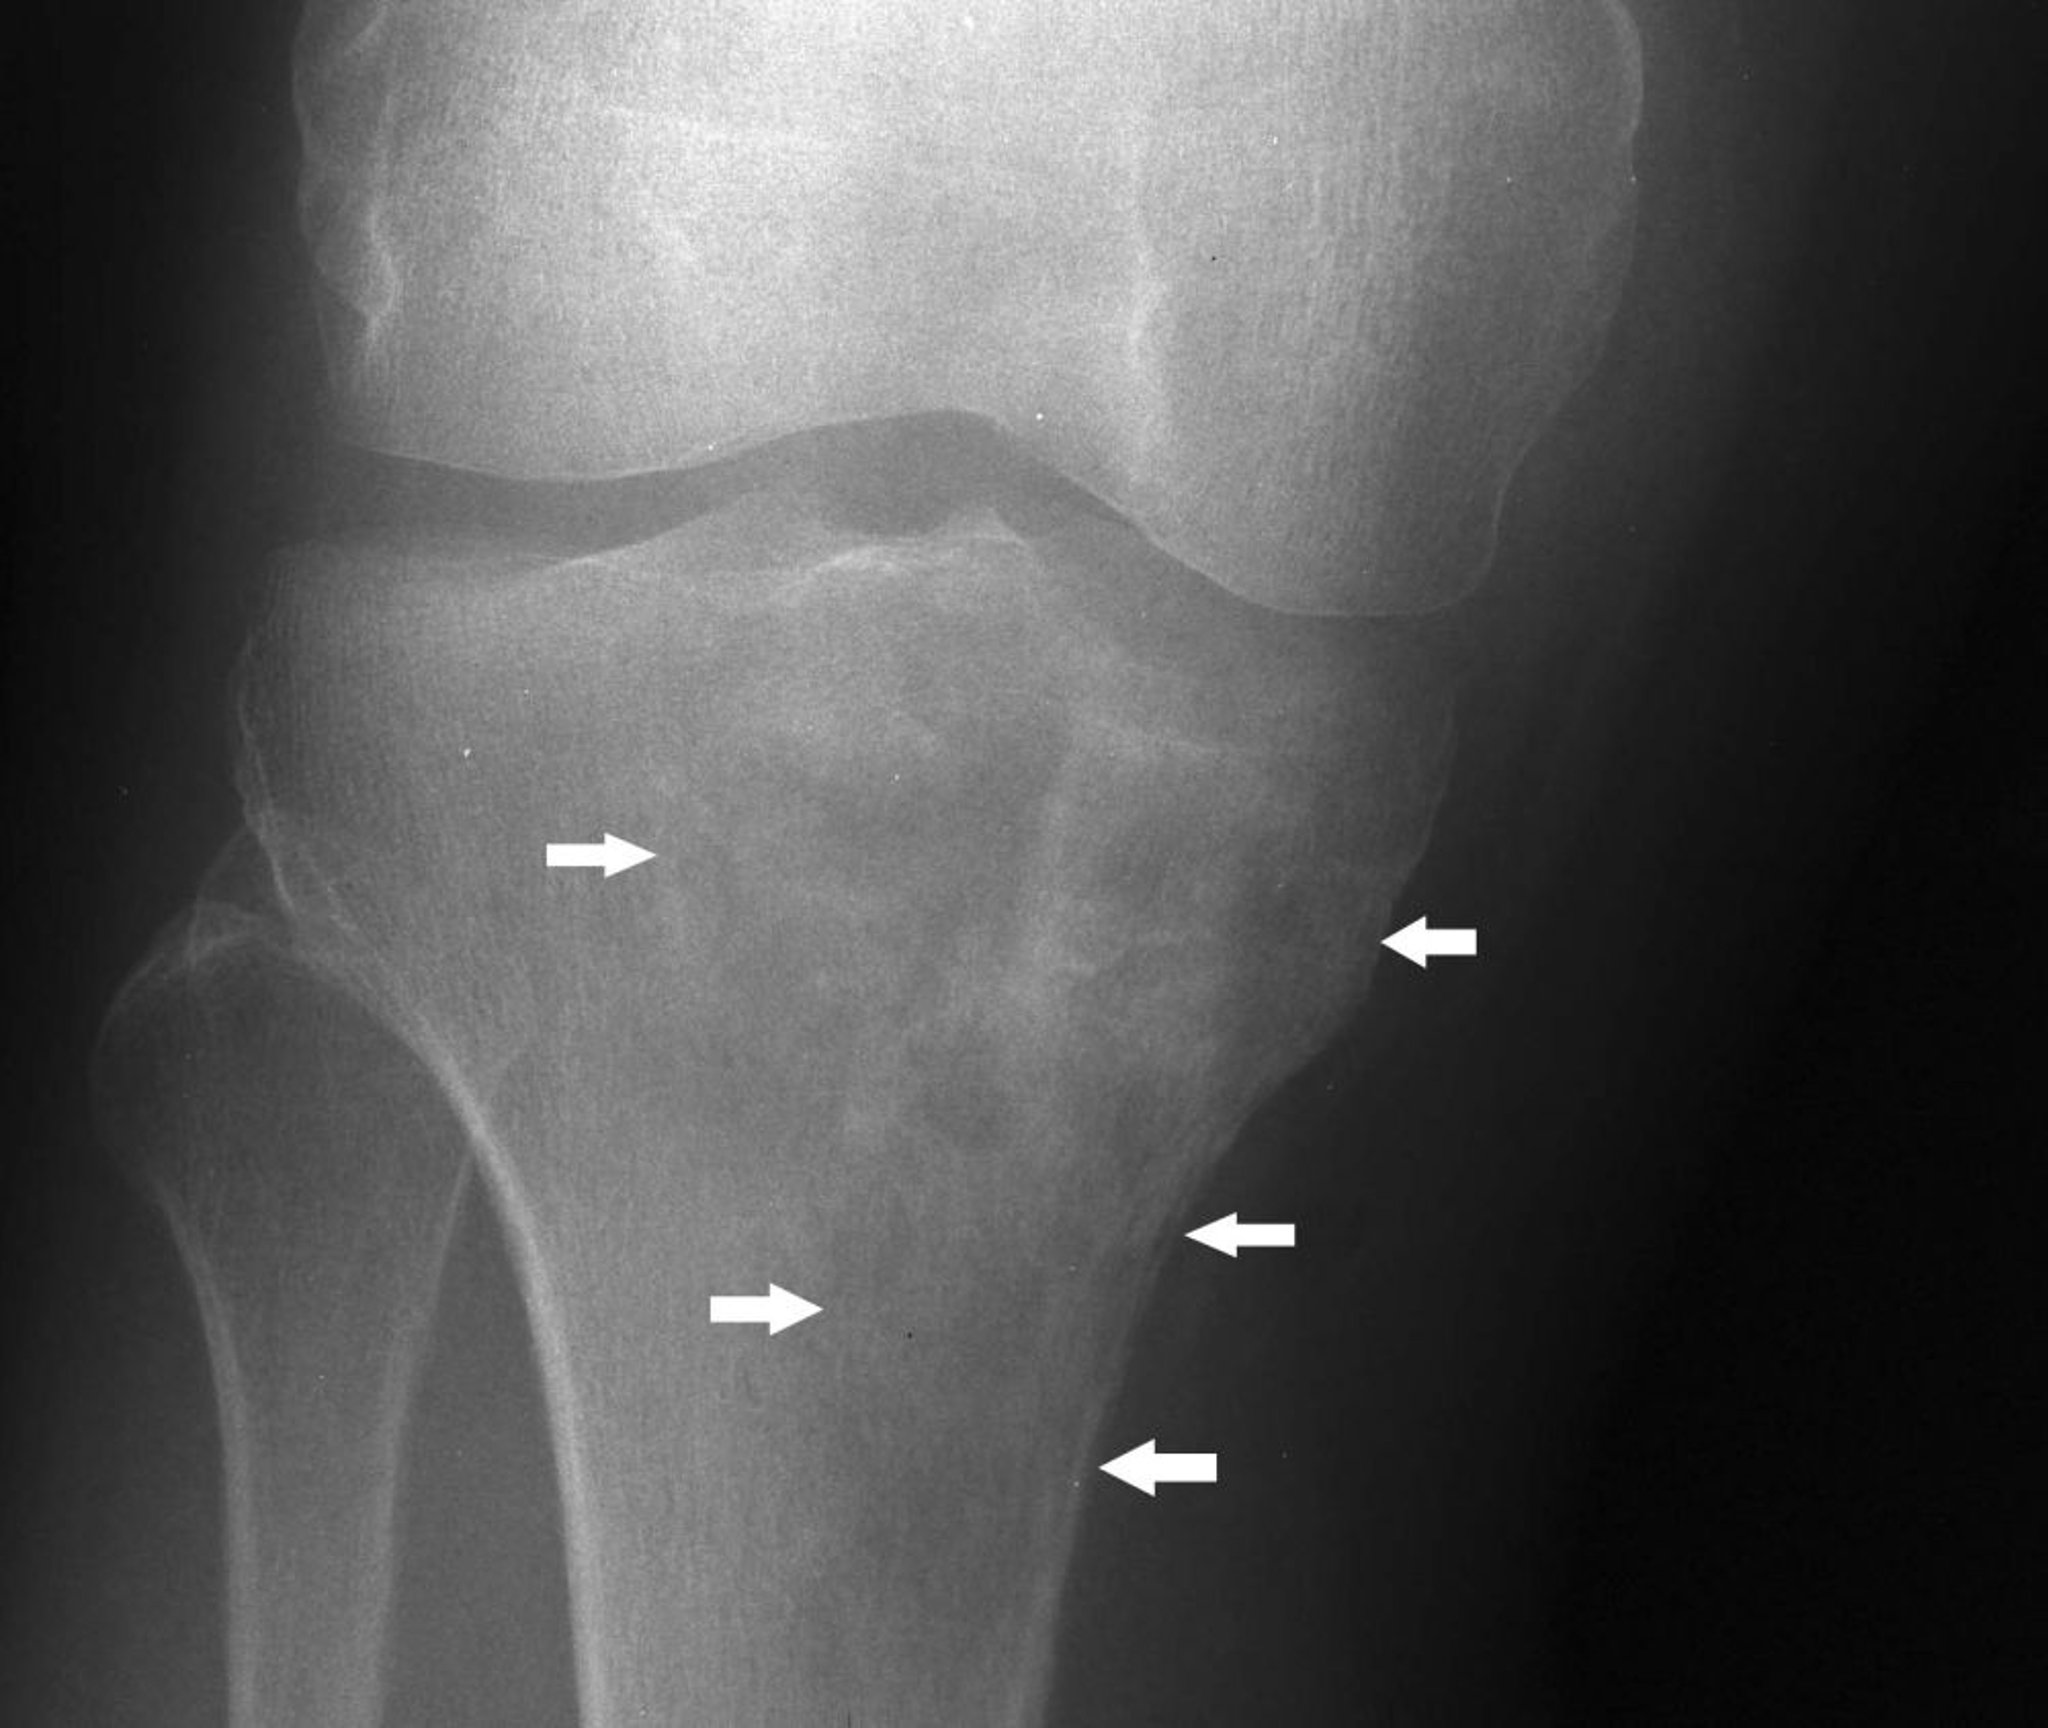

Cette radiographie du genou montre un lymphome dans le tibia proximal avec un aspect mixte lytique et scléreux sous le condyle tibial médial (flèches).